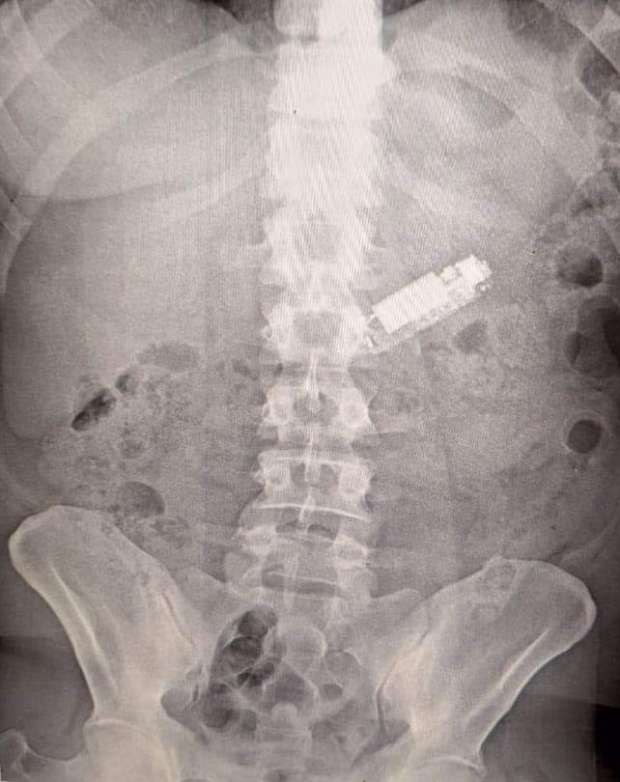

وأوضح أن وحدة الطوارئ بمستشفيات جامعـة طنطـا استقبلت مريضًا في العقد الرابع من العمر يعاني من وجود "هاتف محمول” ابتلعه بطريق الخطأ لمدة 5 شهور داخل البطن وتم إجراء كافة الفحوصات الطبية ومنها أشعة عادية على البطن لتحديد مكان الهاتف المحمول وأشارت الأشعة إلى وجوده داخل المعدة وتم إجراء منظار على البطن استمر لمدة ساعة وتم إخراجه من بطن المريض الذي غادر المستشفى بعد استقرار حالته الصحية.